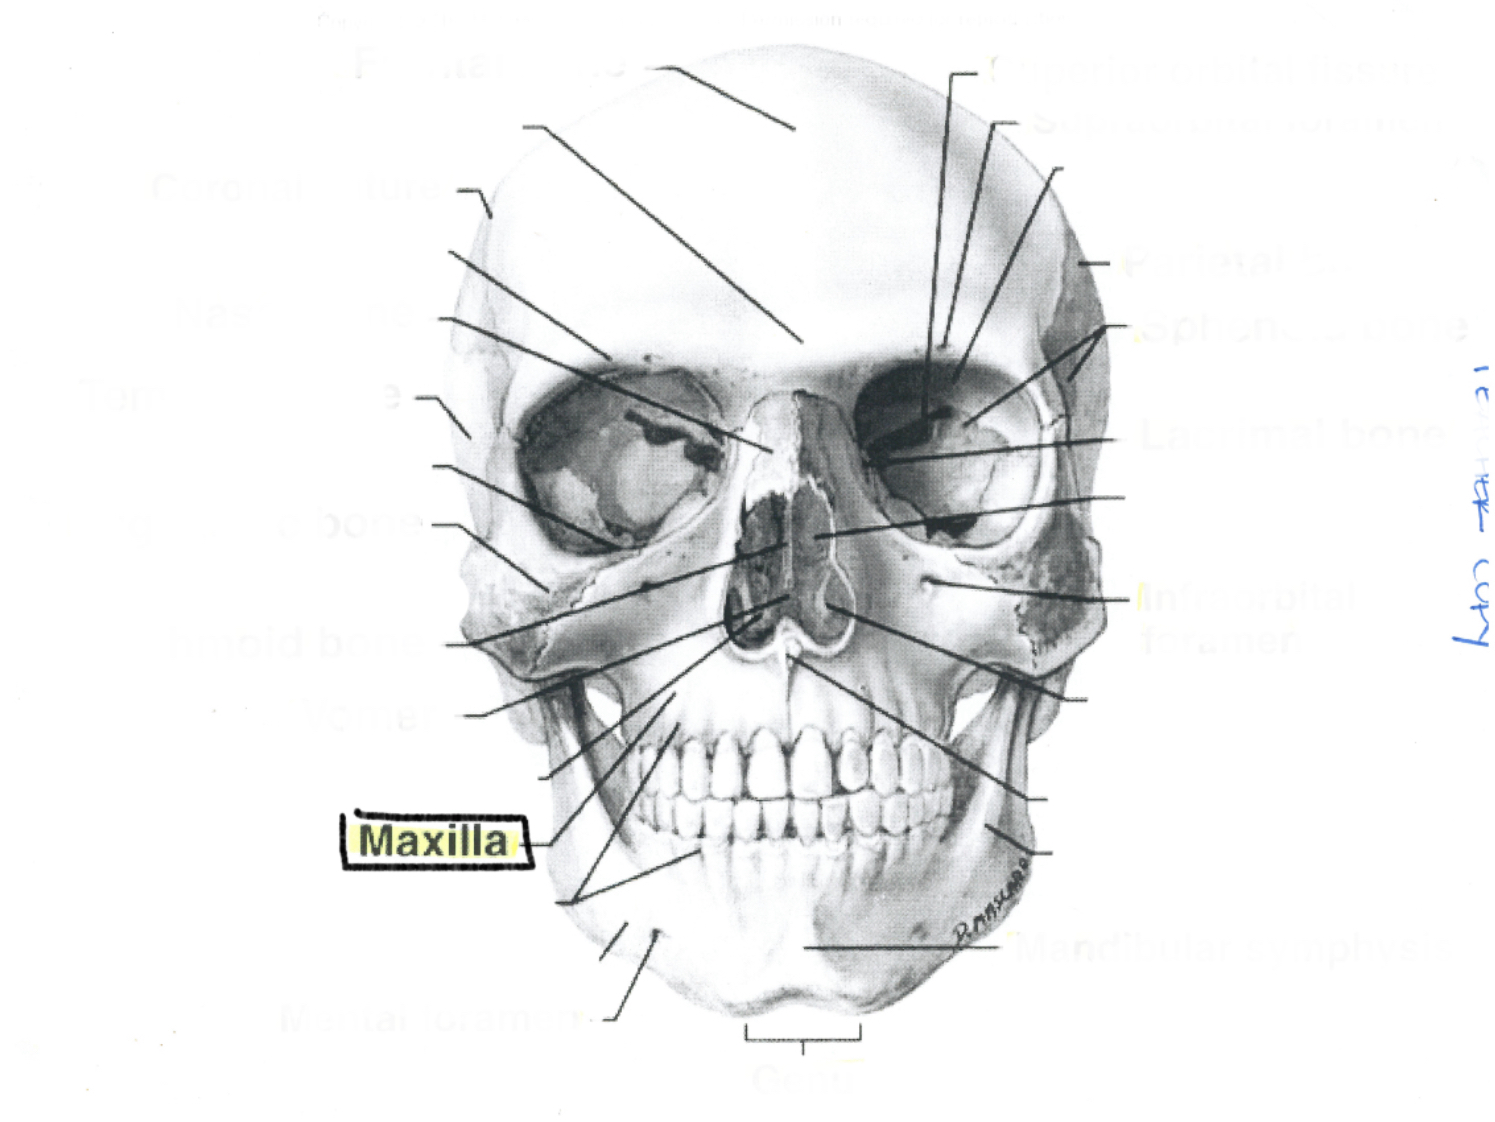

Maxilla